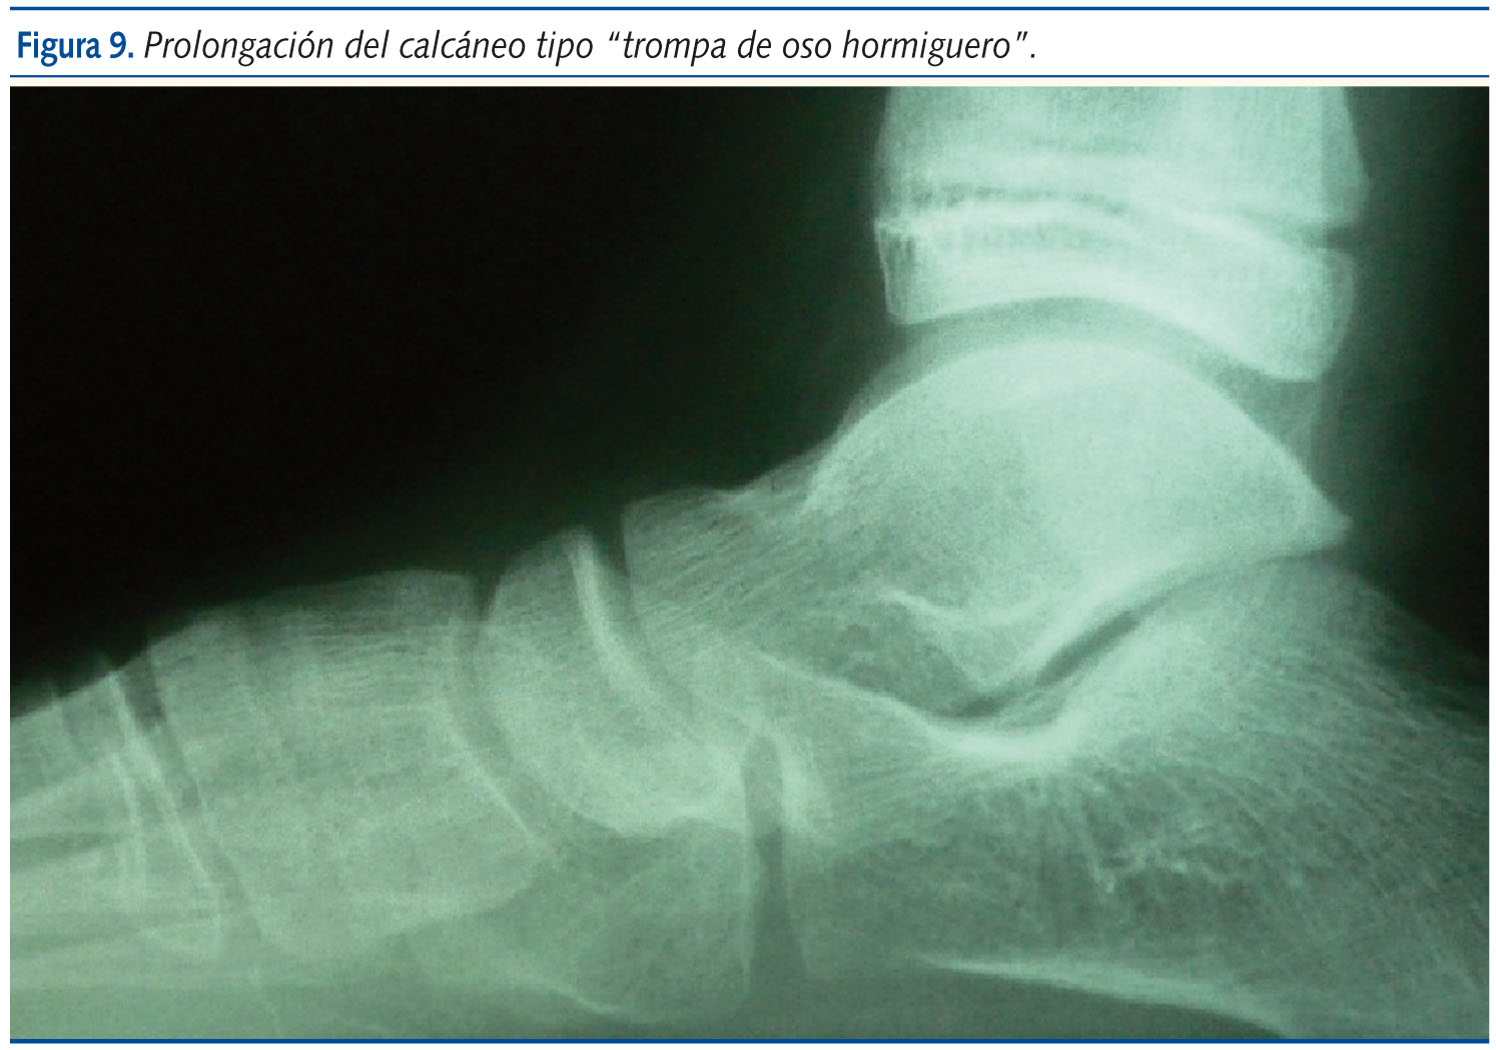

La imagen radiográfica en etapas infantiles es poco demostrativa y solo en casos de mucha espasticidad un buen estudio de resonancia magnética o tomografía computarizada nos indica la zona de fusión. En etapas pre- y adolescentes se encuentra el calcáneo con “morro de oso hormiguero”, que tiende a unirse con el escafoides o termina haciéndolo. Estas suelen ser las barras calcáneo-escafoideas, que son las más sencillas de tratar quirúrgicamente, pudiéndose revertir el proceso si se diagnostica precozmente.

Las barras también pueden estar entre astrágalo y calcáneo, más frecuentes y difíciles de tratar, o bien entre otros huesos del tarso (figuras 8, 9 y 10).